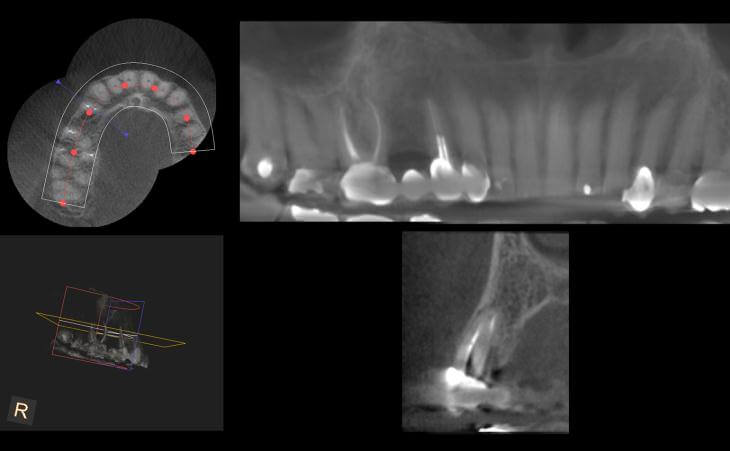

This 74 year old patient was unhappy with her current smile and the existing teeth were unsalvageable. Utilizing computer planning and guided implant placement, the teeth were extracted and implants were placed on the same day. 6 months later, final bridges were made and the patient was thrilled with her new smile.

Patient had a 3 unit bridge that was decayed. A CT scan was taken to evaluate the surrounding bone. Patient underwent extraction and Bone Grafting to regenerate and build the necessary bone for implant placement. Implant was placed. Final x-ray showing 3 implants placed to replace the bridge.

Patient has been missing lower left teeth for years. Developed large ridge defect from not having teeth. Pre surgical CT scan shows thin ridge with inadequate bone volume to place implants. Ridge bone graft was done. Special covering placed and secured. CT scan after 4 months of healing. Final post implant placement x-ray.

This is a 70 year old male who was unhappy with the fit of his lower denture. I placed 4 dental implants to anchor the denture and the patient was very comfortable.

This patient presents missing right and left lower jaw teeth. Jaw bone was regenerated using the latest techniques and 3 dental implants were placed on each side for permanent crowns.